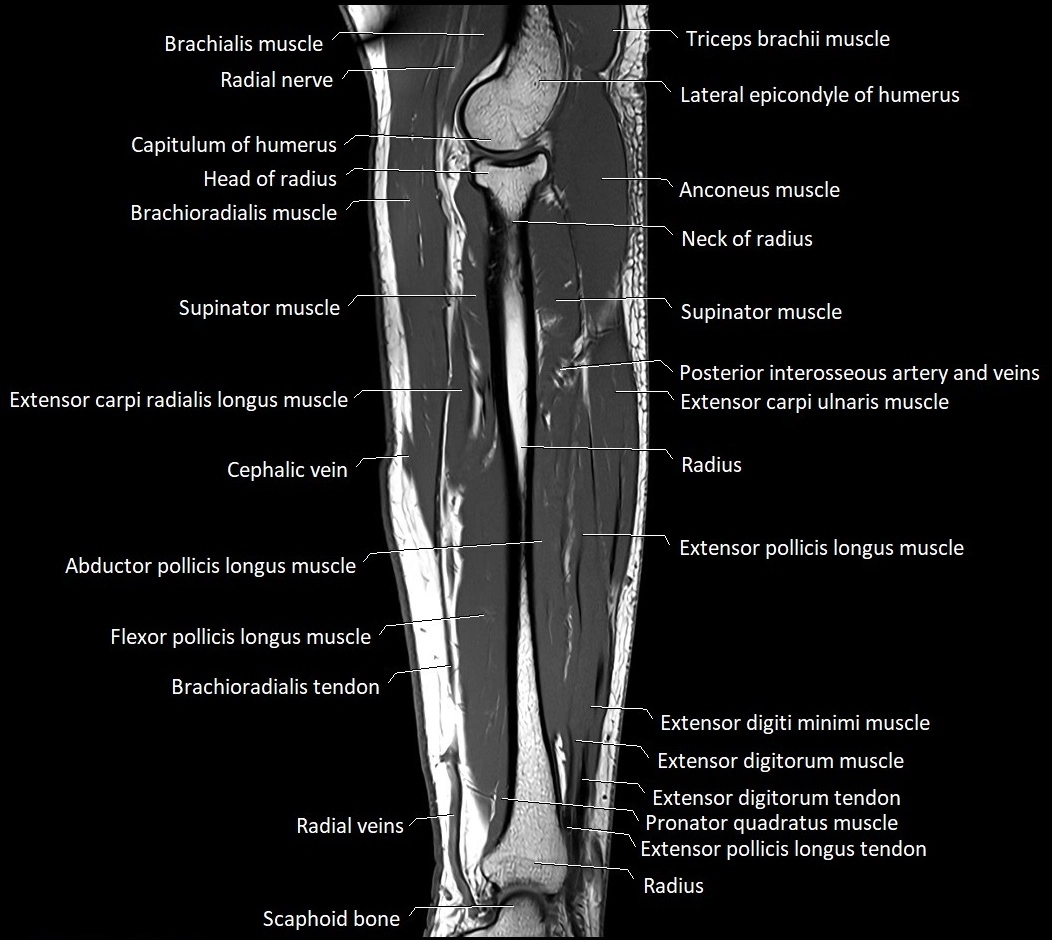

MRI images

image